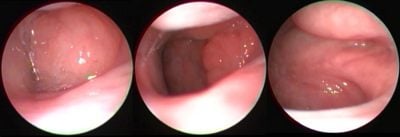

“Büyük geniz eti”, ebeveynlerin sıkça duyduğu ve çocukları için endişelenmelerine yol açan bir durumdur. ...

İlaç tedavileri ile düzelmeyen, ciddi ve inatçı sinüziti olan çocuklarda ameliyat gündeme gelebilir. ...